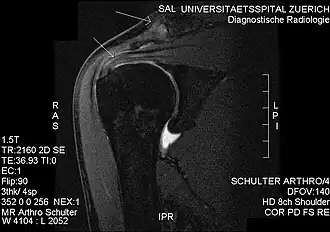

Plain x-rays of the shoulder can be used to detect some joint pathology and variations in the bones, including acromioclavicular arthritis, variations in the acromion, and calcification. However, x-rays do not allow visualization of soft tissue and thus hold a low diagnostic value.[2] Ultrasonography, arthrography and MRI can be used to detect rotator cuff muscle pathology. MRI is the best imaging test prior to arthroscopic surgery.[2] Due to lack of understanding of the pathoaetiology, and lack of diagnostic accuracy in the assessment process by many physicians,[21] several opinions are recommended before intervention.